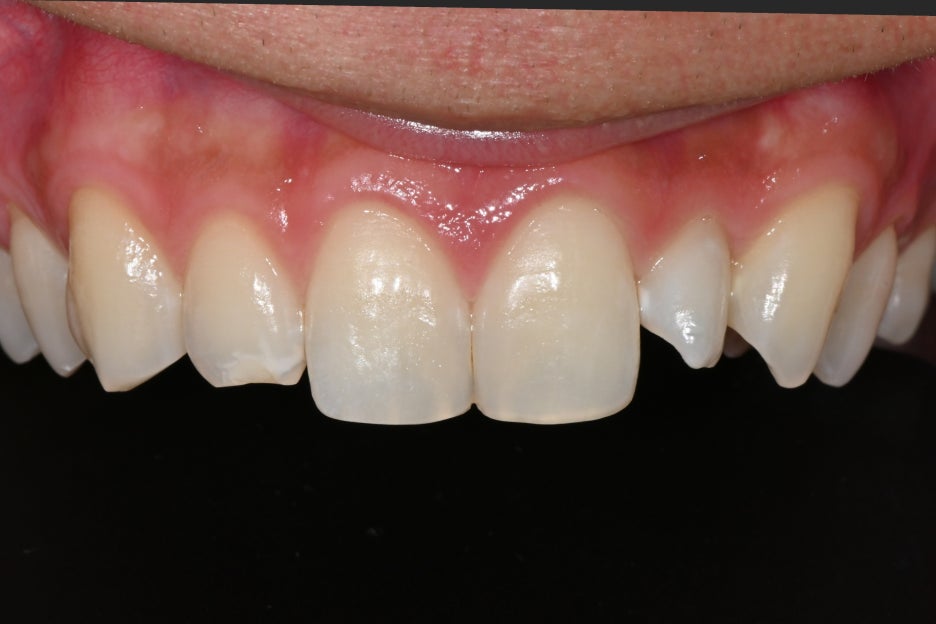

처음 내원 당시 환자분은

1.앞니 옆 치아가 작게 나 있는 형태

2.레진 변색

3.전체적으로 어둡게 보이는 치아 색

이 세 가지 문제로 고민하고 있었습니다.

사람마다 치아 크기와 형태는 다르지만,

양쪽 균형이 크게 다르면 밝기를 높여도

자연스러움이 나오기 어렵습니다.